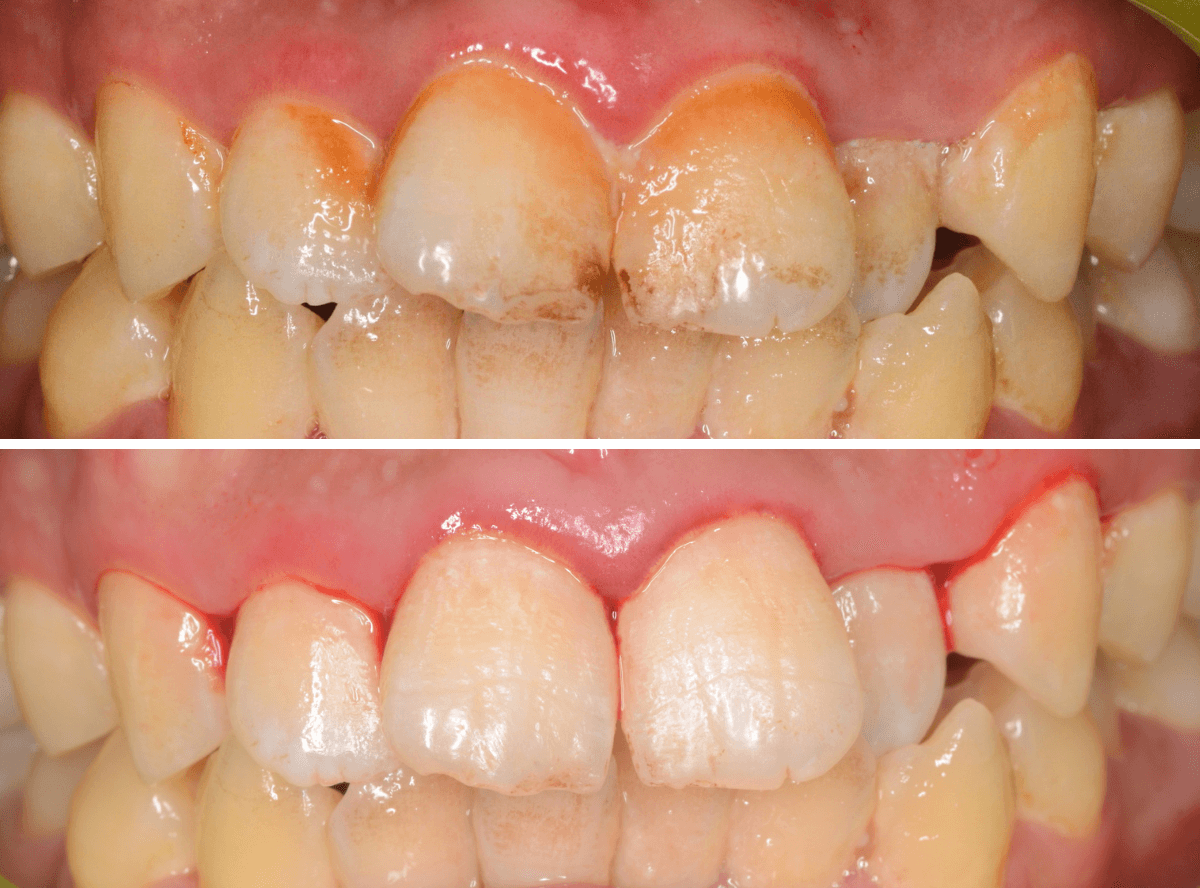

治療前との比較です。

比べると、違いがわかると思います。

その後、この患者さんは熱心に通院とお手入れをされて、約二か月が経ちました。

歯肉は順調に引き締まってきました。

歯周治療は、ご本人のメンテナンスなしには結果が出ません、頑張ってらっしゃる形が見えて、とても嬉しいですね

こちらが比較写真です。

並べてみると、治り具合がよりわかりますね